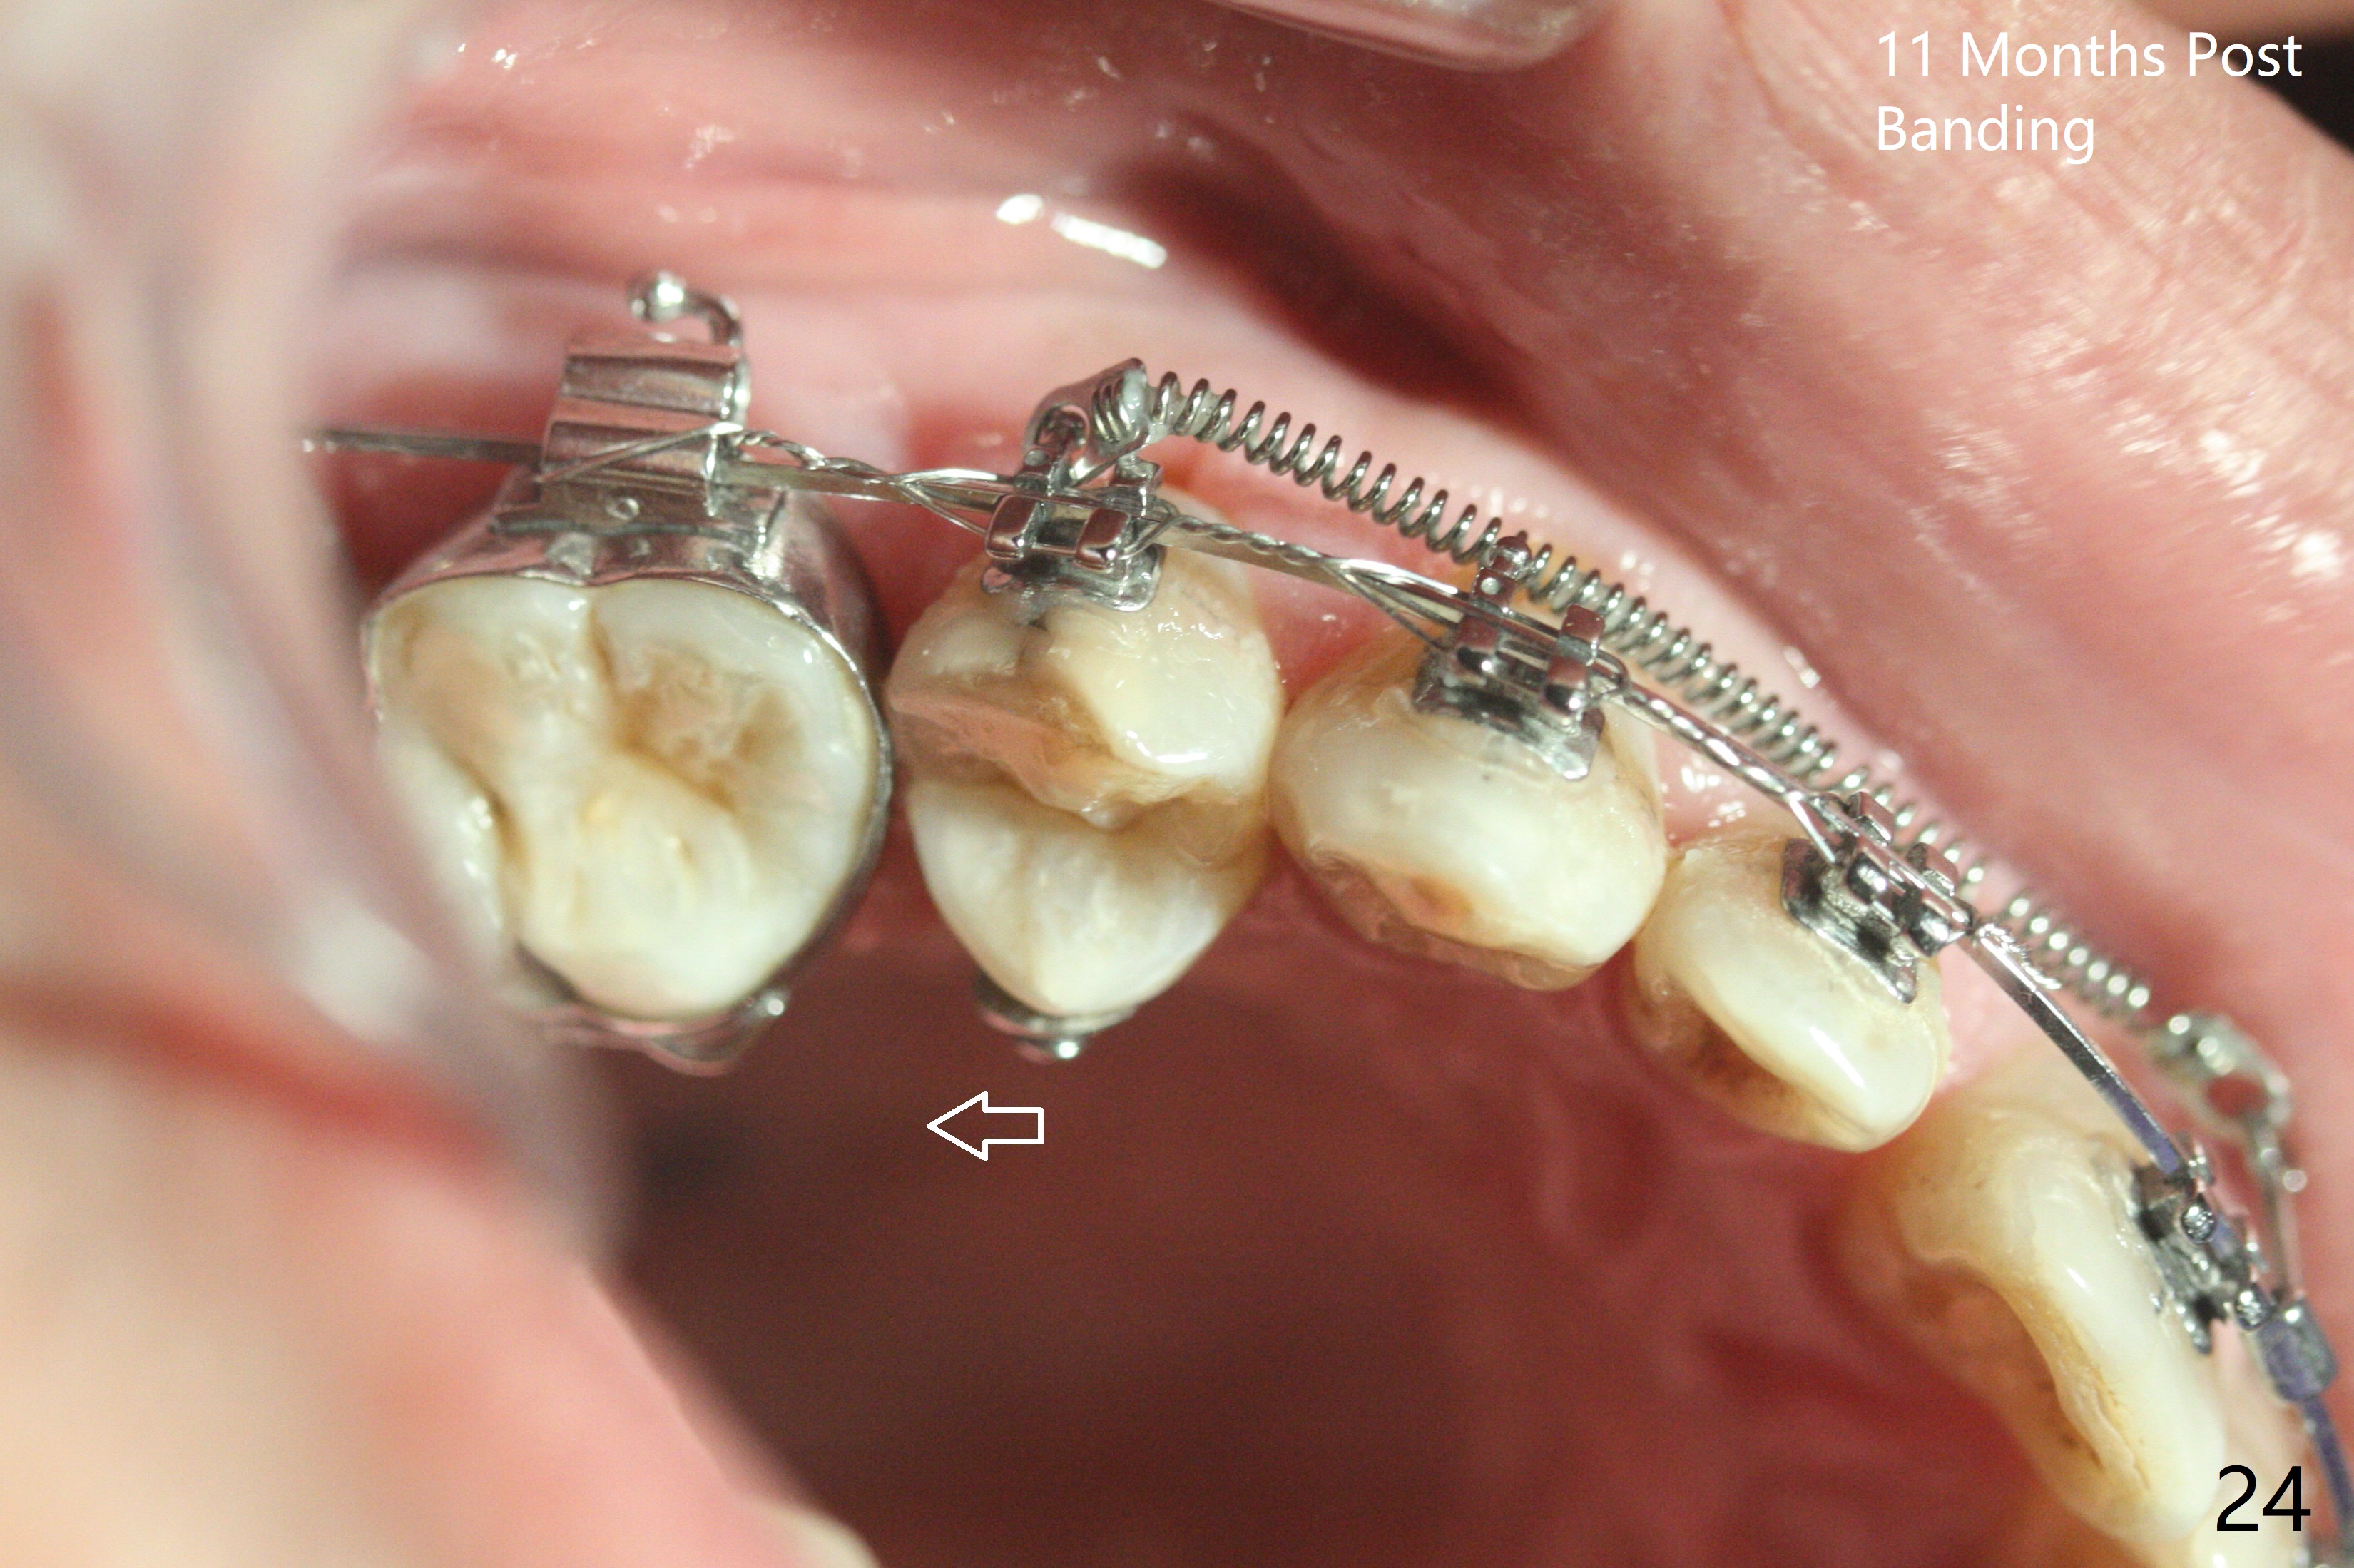

A 40-year-old man requests orthodontics after #17 and 32 extraction. UL5 is missing (Fig.1), while the upper midline deviates to the left (Fig.2 arrow) with crowding between UL2 and 3 (Fig.3). The main goal is to retract UL5 distal and move the upper midline to the right to alleviate UL anterior crowding. Implant will be not needed. To monitor potential root resorption associated with tooth movement, preop PAs are taken (Fig.4-7). The space for an implant at UR5 is narrow. UR4 needs to be distalized using UR7 or a miniimplant distal to UR7 as an anchor (Fig.8). UR4 and 3 will be repositioned to establish Class I occlusion (Fig.9). The space gained by UR4 distalization may be enough to correct the upper midline deviation and UL3 malposition (Fig.10). Brackets will be placed in the lower arch in spite of the normal alignment (Fig.11). UL2 and 3 brackets are unable to be engaged to 14 niti wire (Fig.12). Next visit try to engage UL2 bracket. If not, save the old wire for possible future reuse. Closed spring is placed with 18 ss wire <3 months post banding (coronavirus). Three weeks post closed spring between UR4-7, UR3,4 are being distalized (Fig.13). Distalization of UR4 is not much in 5.5 months (Fig.14,15). It seems necessary to use a miniimplant distal to UR7 as an anchor (Fig.16 white circle), place a long hook mesial to UL4 (more or less root movement instead of tilt) and place the same closed spring between the anchor and hook. In spite of the fact that UR4 seems to have been completely distalized and that UR2 is being distalized 8 months post banding (Fig.18), a 8 mm long mini-implant is placed in the maxillary tuberosity with minimal local anesthetic (Fig.17,19). A longer closed spring (18 mm) is placed between the implant and UR3 hook (Fig.20). Next appointment a lingual button will be placed at UR4 for rotation, while a post hook mesial to UR3 for torque. UR3 distalizes with the help of UR mini-implant, which is unfortunately loose. Next visit place lingual button at UR4 (Fig.21 arrow) to distalize the lingual cusp. Crimpable power hook is placed mesial to UR2 for distalization (for root torque, Fig.22). If it works, remove the wire and reposition the hook for UR1 next visit. UR2 is distalized in one appointment (~ 1 month, Fig.23, as compared to Fig.22). With lingual button at UR4, rotation seems to have been corrected shortly (Fig.24 arrow).